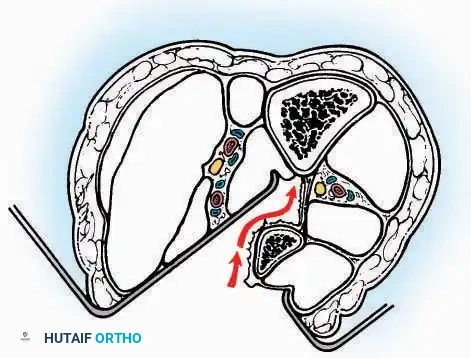

* Muscle Management: Identify the origin of the extensor digitorum brevis (EDB) muscle on the lateral calcaneus. Divide it in the direction of its fibers, or detach its origin entirely and reflect it distally to expose the subtalar and calcaneocuboid joints.

* Deep Exposure: Retract the extensor digitorum longus (EDL) tendons, the dorsalis pedis artery, and the deep peroneal nerve (DPN) medially. Incise the anterior ankle capsule to expose the tibiotalar joint.

* Tarsal Exposure: Expose the talonavicular joint by dissecting deep to the extensor tendons and incising its capsule transversely. Continue laterally through the capsule of the calcaneocuboid joint. By excising the fat pad within the sinus tarsi (lateral and inferior to the talar neck), the posterior facet of the subtalar joint is brought into direct view.